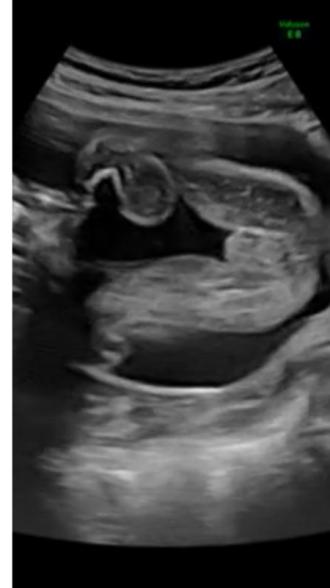

初めまして(^^)今日1ヶ月検診に行ってエコーで赤ちゃんをみてきました(^^)

前回のエコー検査で「あー女の子っぽいね〜」って言われたんですけど女の子と言われていてもおちんちんが隠れていてって事もあるみたいで(O_O)

今日のエコーで股の所が写ったけれど自分ではイマイチわかりません(*_*)

しかも先生にも聞けなくて写真があるので分かったら教えていただきたいです^_^

お腹の赤ちゃんのエコーについてですね。

足を開いているような様子ですので、隠していることもなさそうかなと思います。

先生がお話しされていたように、女の子なのかなと思いました。

また次回の健診のさいに確認をしてみてください。